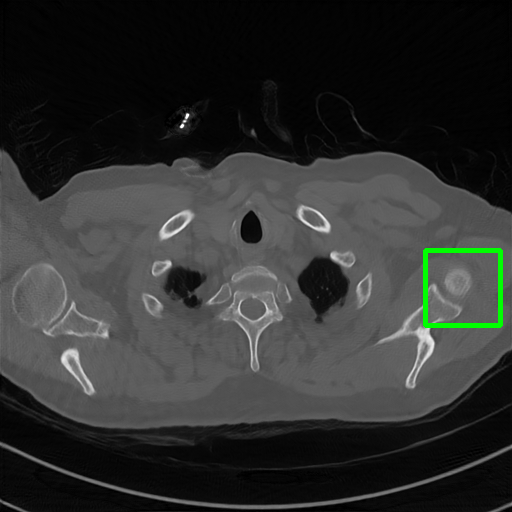

Qualitative comparison. We also visualize the reconstructed images of these methods in Fig. 4 with = [72, 96 ,144] (See more visualizations in Appendix). In all three rows, our DuDoTrans shows better detail recovery, and sparse-view artifacts are suppressed. Further, when decreasing , where raw sinograms are too messy to be restored and low-quality images from FBP are too hard to capture global features, Transformer-based models exhibit reduced performance. The phenomena suggests that we should design suitable structures with the Transformer and CNNs, facing with different cases.

Ground Truth

FBP

FBPConvNet

DuDoNet

ImgTrans

DuDoTrans